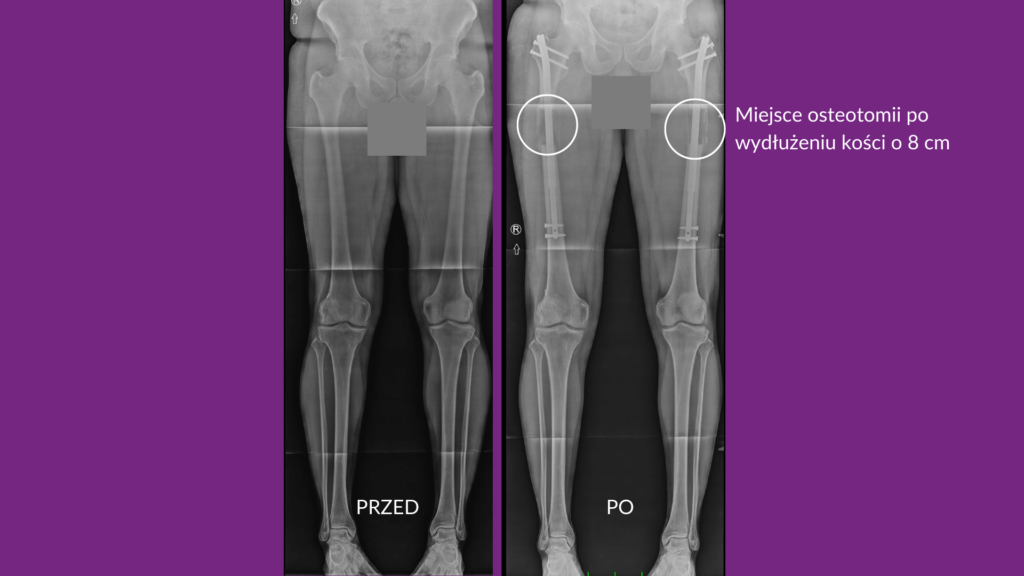

Zabieg estetycznego wydłużania kończyn przeprowadzany jest w znieczuleniu ogólnym. Po nacięciu skóry, chirurg przecina kość, wprowadza do jej wnętrza specjalny implant i zamyka ranę. Następnie Pacjent przechodzi przez okres rekonwalescencji.